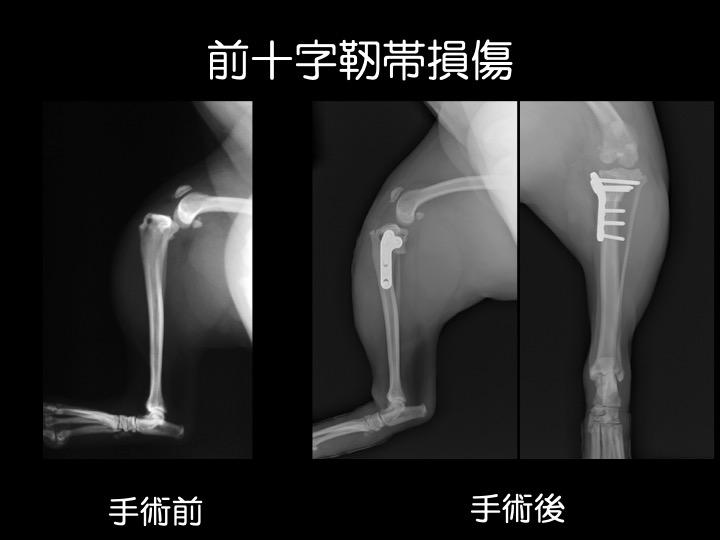

・前十字靭帯は、大腿骨(太ももの骨)と脛骨(スネの骨)を結ぶ靱帯で、大腿骨に対して脛骨が前方に飛び出したり内側にねじれないように支える役割があります。

・肥満、加齢、慢性の膝蓋骨脱臼(特に小型犬)による靭帯の脆弱化などが原因で、前十字靱帯は切れやすくなります。靭帯の損傷によって、痛みや、足を挙げたりかばったような歩き方などが見られます。

・治療は、鎮痛剤などによる内科治療もしくは外科手術となります。手術は、ラテラルスーチャー(関節外制動法)とよばれる、脛骨が前方に変位かつ内旋しないよう膝関節に糸をかける方法を用います。

・中〜大型犬では、より術後早期の回復が期待できる「TPLO(脛骨高平部水平化骨切り術)」という手術を実施している高度医療施設へのご紹介も行なっております。